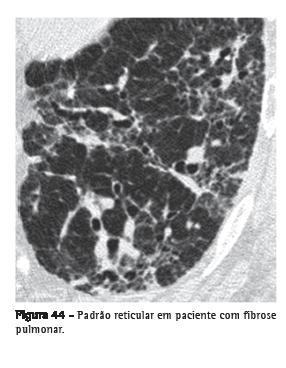

Padrão reticularAlteração, usualmente relacionada às doenças intersticiais, caracterizada nas radiografias por inúmeras pequenas opacidades lineares que resultam em uma aparência de rede.(1) Na TCAR, é possível individualizar os componentes responsáveis por esse padrão na radiografia, que usualmente estão relacionados à presença de linhas intralobulares e septais (Figura 44) ou à presença de cistos cujas paredes se apresentam como linhas na radiografia, como nas doenças císticas pulmonares, no enfisema associado a bolhas e até mesmo nos cistos de faveolamento.(1,3,7)

Ver também Linhas intralobulares.